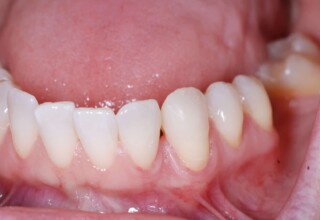

Full mouth prosthetic reconstruction on implants with a different approach on upper and lower jaw

Lower jaw: extractions, direct implant placement and immediate loading (same day) with a transitional bridge.

Upper jaw: Sequential extractions, sequential implant placement and gradual incorporation in the temporary bridge so that the patient was never left without fixed teeth. The aim of the above approach was to have the patient in continuous functional and aesthetic reconstruction, without immediate loading due to anatomical restrictions. Old smiling photos of the patient were used because the natural shape of the teeth was completely lost due to repetitive prosthetic attempts. Tooth relationship and teeth-lip support was transferred to the temporary restorations. Two different transitional bridges were needed to fully estimate phonetics, mastication and esthetics. After the necessary adjustments were finalized, the temporary bridge was used as a guide for the permanent bridges.